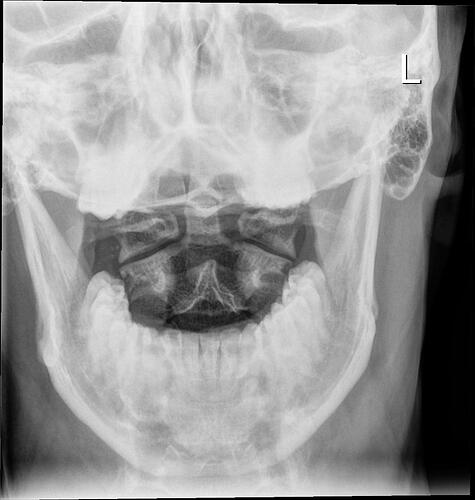

A few days ago, I started having swallowing difficulties. When I reached to the back of my mouth with my finger, I was shocked to feel a bony structure instead of the normal soft tissue. Since it was late and I had little access to my GP, I used ChatGPT, which suggested it might be Eagle syndrome. I then did some research and found your group.

What worries me is that my oxygen supply to the brain may have been limited for so long that it caused structural neural damage. I will ask my GP and push hard for a CT scan of my neck. But I want to ask you: have any of you had similar issues, and after the operation, did your symptoms—even if severe initially—resolve completely, especially cognitive ones?